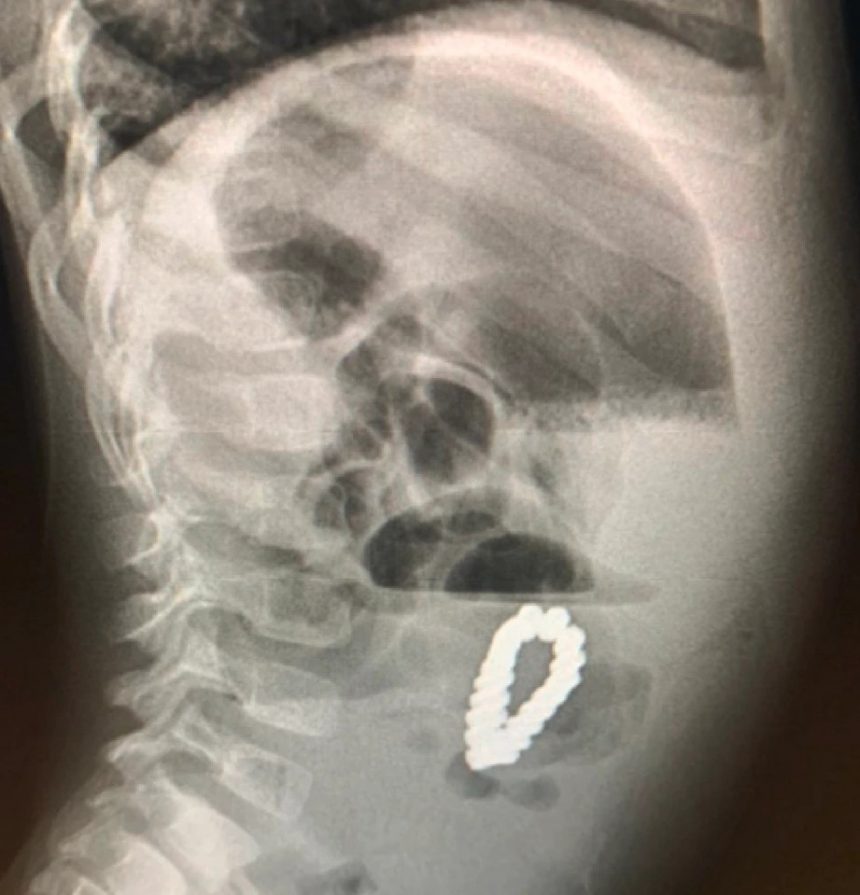

Пет дена по процедурата, лекарите направиле повторен ултразвук и откриле нараквица во стомакот на детето. Малото момче имало итна лапаротомија за да се отстрани предметот – за кој се покажало дека е нараквица составена од 18 магнетни зрнца во хексагонална форма. Нараквицата му ги попречувала цревата, како и ископала четири мали дупки во нив, кои лекарите можеле да ги поправат.